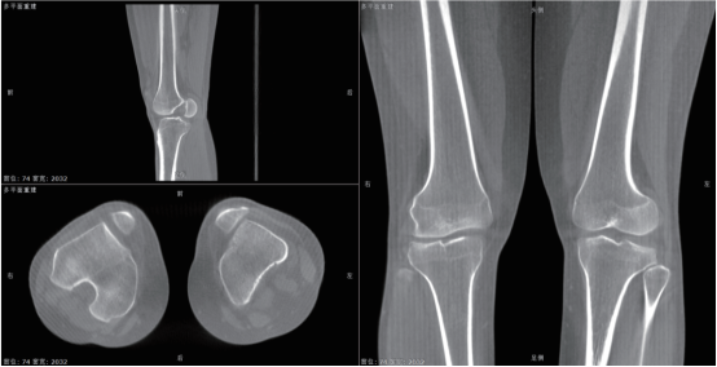

该系统核心优势在于整合动态透视与三维成像技术。在脊柱全长摄影、双下肢负重位检查中,可一次性获取颈椎至骶尾椎的高清全景影像,避免传统分段拍摄的拼接误差,为脊柱侧弯、关节畸形等疾病的力线测量和手术规划提供精准数据。其动态功能成像模块能实时捕捉关节运动状态下的解剖结构变化,清晰显示膝关节屈伸、肩关节活动时的软组织动态,显著提高韧带损伤、关节不稳等隐匿性病变的检出率。

医院将以该设备为依托,构建“影像检查-功能评估-治疗方案”一体化诊疗路径。如针对脊柱侧弯患者,可同步完成影像采集与三维力线分析,关节术后患者可通过动态成像评估康复进展,实现个性化治疗方案优化,进一步深化影像科与骨科、康复科、运动医学科的多学科协作。